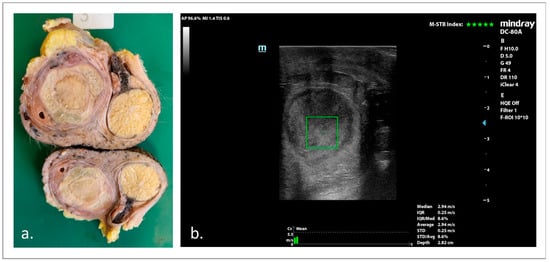

3.3. B-Mode and Doppler US Examinations

3.4. SWE Examinations